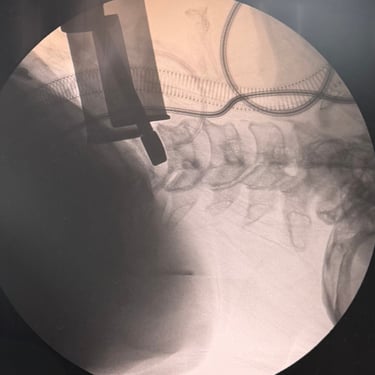

Hernia Cervical con Mielopatía: ACDF con Cage y Placa asistida con Monitoreo Neurofisiológico

La hernia cervical con mielopatía se produce por la compresión de la médula espinal, ocasionando dolor cervical, debilidad, alteraciones sensitivas y trastornos de la marcha. En casos de compromiso neurológico progresivo, la discectomía cervical anterior y fusión (ACDF) con cage y placa es una alternativa quirúrgica eficaz. La cirugía asistida con monitoreo neurofisiológico intraoperatorio permite evaluar en tiempo real la función neurológica, aumentando la seguridad del procedimiento. Este abordaje facilita una descompresión adecuada, estabilización del segmento cervical y favorece una recuperación neurológica segura y progresiva.